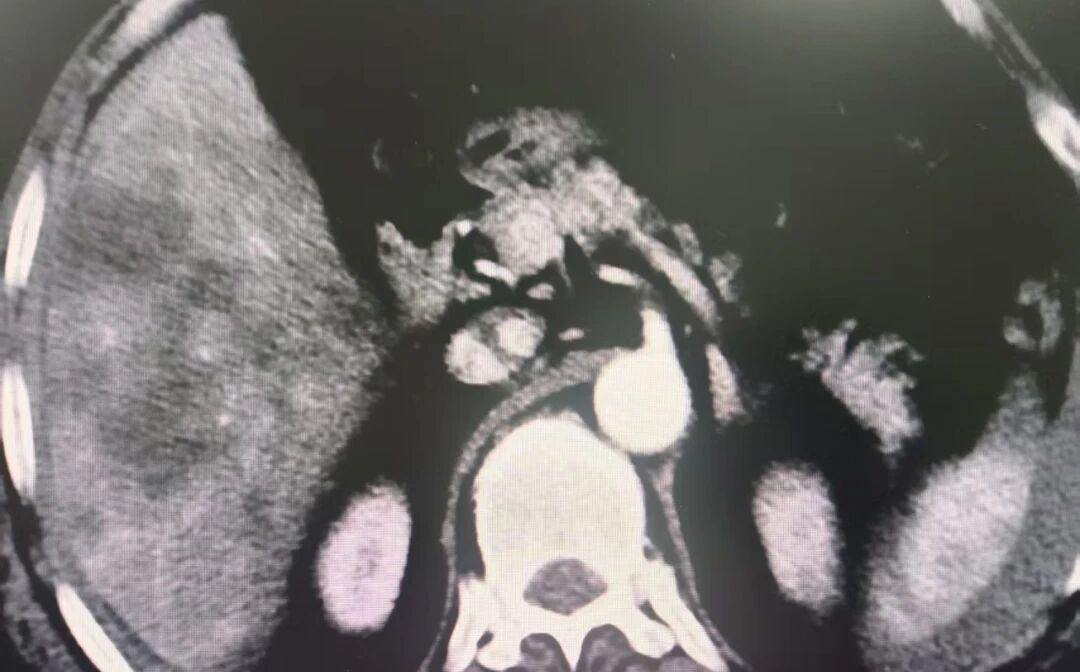

患者艾某,今年60岁,前段时间因“外伤致腹痛1日”进入库车市医共体总院人民医院治疗。经检查,确诊为肝破裂合并腹腔大出血及胆漏,需手术治疗。然而,传统肝破裂手术需20厘米以上腹部切口,创伤大、恢复慢。

裘铠杰医生与普外二科团队研判患者病情后,决定采用腹腔镜下肝破裂肝部分切除术。9月15日,裘医生指导医院多学科团队仅通过三四个0.5-1厘米小孔就成功完成手术。术后,患者各项生命体征平稳,恢复良好。